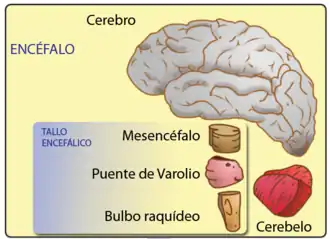

Encéfalo

O encéfalo é o centro do sistema nervoso em todos os animais vertebrados, e em muitos invertebrados. Alguns animais primitivos como os celenterados e equinodermes como a estrela-do-mar possuem um sistema nervoso descentralizado sem encéfalo, enquanto as esponjas não possuem sistema nervoso. Nos vertebrados o encéfalo localiza-se na cabeça protegido pelo crânio, próximo aos aparatos sensoriais primários: visão, audição, equilíbrio, paladar, e olfato. Os encéfalos podem ser extremamente complexos. O encéfalo humano - composto dentre outras estruturas pelo cérebro, cerebelo e tronco encefálico (Mesencéfalo, Ponte e Bulbo) - contém cerca de 86 bilhões de neurônios, ligados por mais de 10 mil conexões sinápticas cada.[1][2] Esses neurônios comunicam-se por meio de prolongamentos citoplasmáticos denominado axônio, que conduzem pulsos em sinais chamados potencial de ação para partes distantes do encéfalo e do corpo e as encaminham para serem recebidas por células específicas.

Anatomia

1. Encéfalo frontal

2. Telencéfalo

3. Diencéfalo

4. Tronco cerebral

5. Mesencéfalo

6. Ponte

7. Bulbo raquidiano

8. Cerebelo

9. Medula espinhal

O tronco encefálico, semelhante a um talo, se fixa e deixa o cérebro no início da área do mesencéfalo. O tronco cerebral inclui o mesencéfalo, a ponte e o bulbo raquidiano. Atrás do tronco cerebral está o cerebelo (latim para pequeno cérebro).[6]